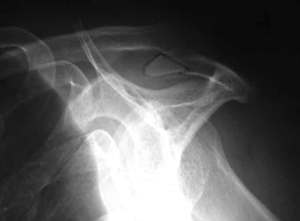

This is an example of a patient with a type III acromion:

Dr Bigliani classified the acromion shapes based on x-rays of the shoulder in the “supraspinatus outlet view”.

They were classified into Type I, II or III acromion.

Dr Bigliani found that those with type III acromion (i.e. with a big hooked spur) had the highest incidence of rotator cuff (shoulder tendon) tears.

This was followed by type II acromion and very little tears in those with type I acromion.

Hence a person with type II or type III acromion is more likely to develop shoulder impingement. This may, over time, become a torn cuff tendon.